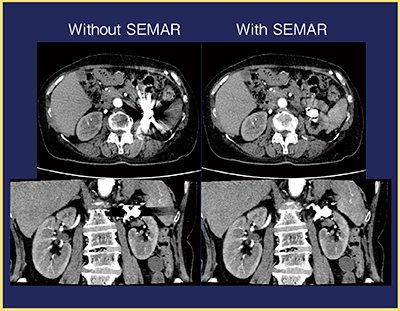

SEMARにより,金属アーチファクトは顕著に軽減され,かつ再構成時間は従来とほとんど変わらないことから,体内金属のある症例にはSEMARの使用が推奨される(図2)。

図2 SEMARの有無による金属アーチファクトの比較

SEMARを用いると,膵臓付近のアーチファクトが

顕著に軽減されている。